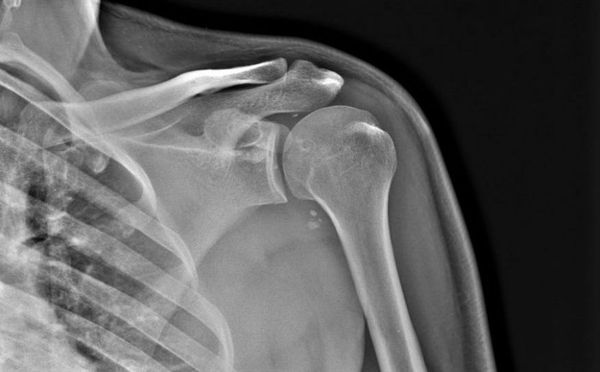

Рентген плечевого сустава в двух проекциях (прямой и боковой снимок) показывает довольно подробную картину патологических изменений. Кроме состояния самого сочленения, с его помощью можно оценить состояние ключицы и лопатки. Благодаря прямой проекции врач определяет степень смещения переломов (если таковые есть), на боковых снимках (аксиальных) хорошо видны изменения краев вертлужной впадины.

Так, при переломах, обычно происходящих с ключицей или плечевой костью, видна линия нарушения целостности костных формирований (также она визуализируется при наличии трещин). Она может быть единственной, когда перелом не осложненный. Но при наличии осколков таких линий бывает несколько. Также на снимках определяется и степень повреждения осколками мягких тканей. При вывихах, когда головка плечевой кости «выворачивается» из суставной впадины, это также четко фиксируется на рентгенограммах.

Изучив несколько проекций плеча, можно определить, в какой точке произошел разрыв капсулы сустава, поврежден ли суставной хрящ. Также легко можно «увидеть» наличие обширных гематом (кровоизлияний), разрывы связок и мышц.

Особо важна диагностика при выявлении патологических изменений различных отделов периферического скелета. С помощью рентгена плечевого сустава (фото представлено выше) выявляют переломы, вывихи, заболевания инфекционной и опухолевой природы. Все структуры сочленения, соседние мягкие ткани из-за различной плотности хорошо визуализируются, вплоть до малейших подробностей. Исследование относится к специфическим, на снимке четко видно какая именно патология возникла у человека.

Чтобы понять, какие именно отклонения выявились на снимке, нужно знать, как выглядит снимок после проведения рентгена плечевого сустава в норме. Врач различает потемнения, видит наличие просветов в структуре костной ткани, определяет ее изменения, а также безошибочно находит очаг заболевания. Нормы показателей:

- Контуры костей четкие, ровные. Костная структура не изменена.

- Полное соответствие формы соприкасающихся суставных поверхностей.

- Суставные щели хорошо прослеживаются, не сужены.

- Контуры смежных поверхностей с обеих сторон четкие, ровные. Костных разрастаний не отмечается.

- Костно-дистрофических изменений, а также дистрофических или травматических не выявлено.

- Мягкие ткани не изменены.